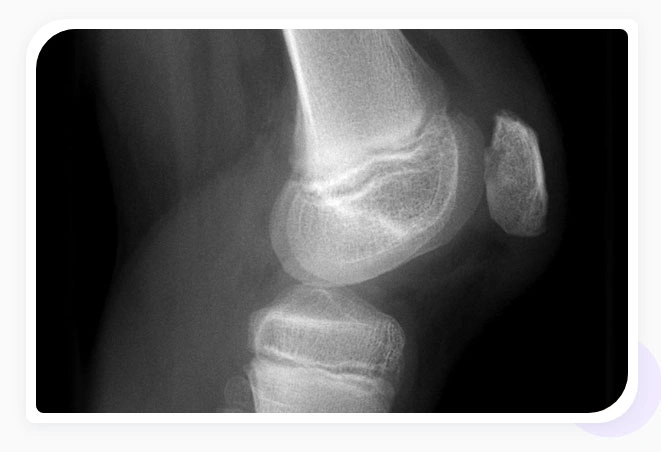

- Imaging with X-Rays or MRI: X-rays can diagnose osteoarthritis of the knee which can co-occur with chondromalacia but are not sufficient to diagnose chondromalacia. Blood tests can rule out other forms of arthritis. More advanced imaging like magnetic resonance imaging (MRIs) will be required to determine the extent of damage to the knee.